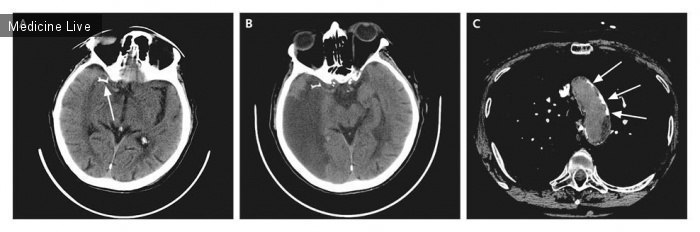

бральная эмболия

Церебральная эмболия 111 фотографий